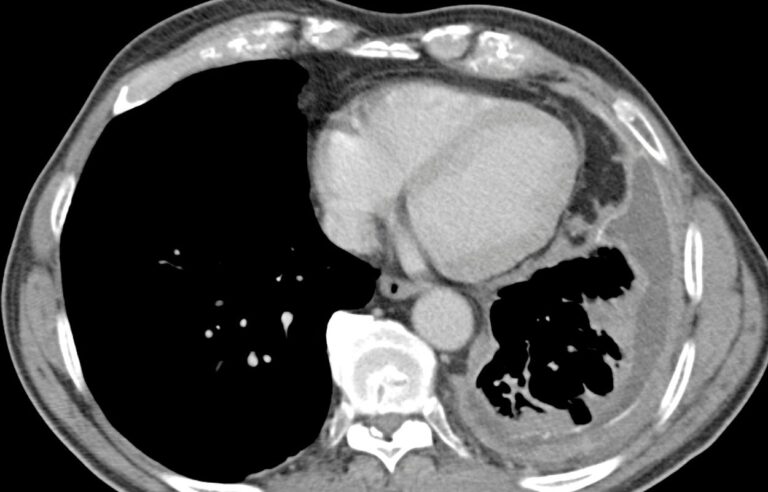

Diagnosing mesothelioma is challenging due to its long latency period and symptoms that mimic other conditions. The diagnostic process typically includes:

• Imaging tests: X-rays, CT scans, PET scans, and MRIs help detect abnormalities.